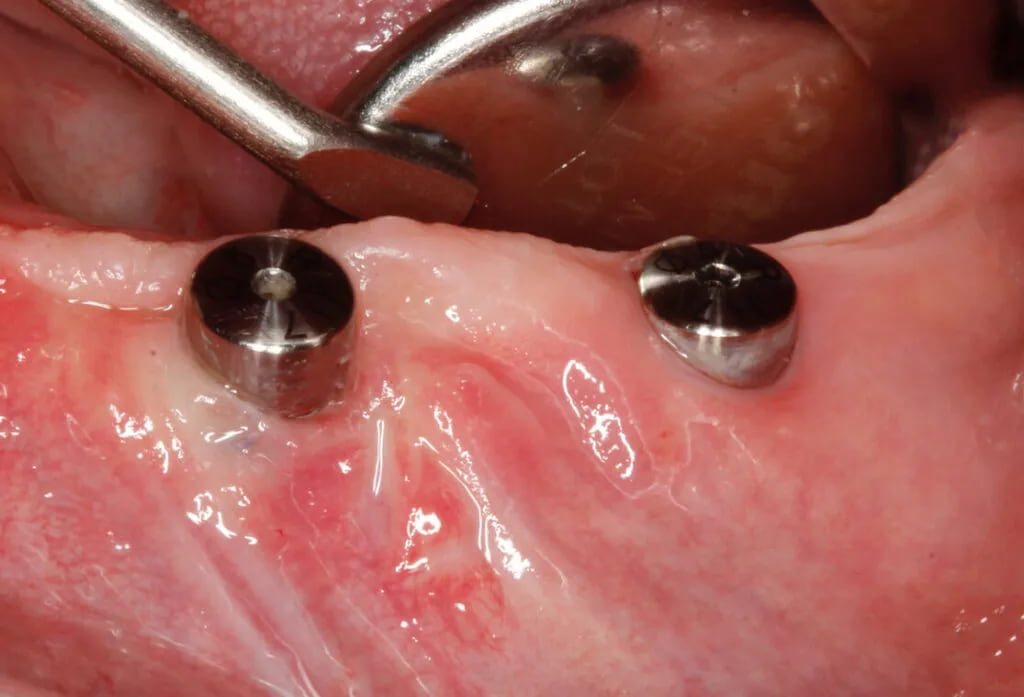

Leczenie implantologiczne w odcinku funkcjonalnym i peri-implantitis

Trudno wyobrazić sobie dziś nowoczesne koncepcje leczenia stomatologicznego bez wykorzystania implantów. Niestety znaczna część pacjentów jest narażona na wystąpienie powikłań biologicznych w postaci peri-implant mucositis i peri-implantitis.

Leczenie implantologiczne w odcinku estetycznym i zaawansowane techniki rekonstrukcyjne

Pozycjonowanie implantów stomatologicznych w strefie estetycznej wciąż stanowi duże wyzwanie w praktyce klinicznej. Lekarz musi rozważyć szeroki zakres różnych koncepcji i technik chirurgicznych, aby dokonać właściwego wyboru i odpowiednio zaplanować leczenie.